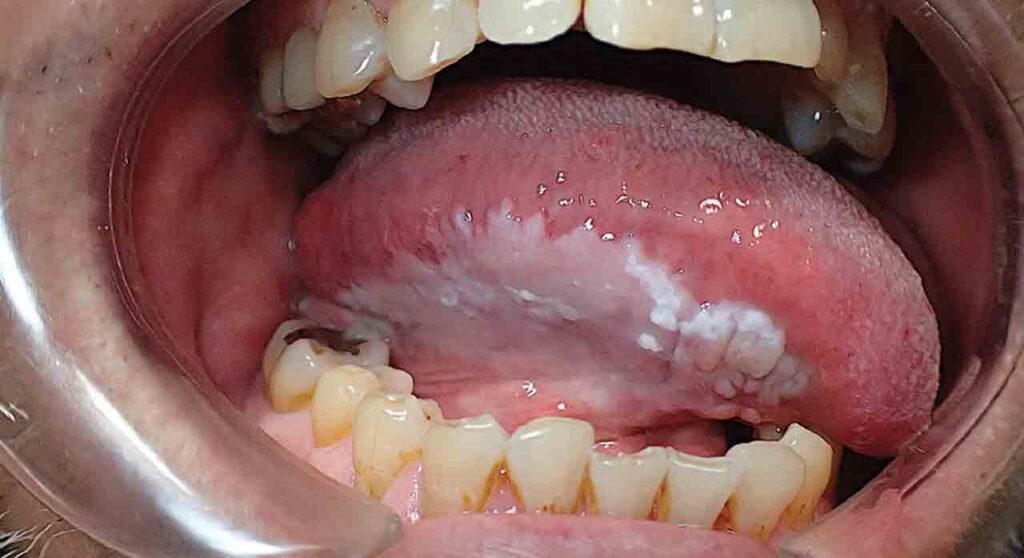

Leukoplakia is a white plaque or patch of questionable risk that may or may not develop into cancer. It is found inside the mouth, commonly affecting the vestibule, palate, lateral surface of the tongue and gums. Tonsils, soft palate, and other parts can also be affected.

Yet another condition, termed oral hairy leukoplakia, also occurs due to the Epstein-Barr virus. It has hairy patches that appear like hair emerging out of the folds in the tongue.

Leukoplakia typically affects the gums, cheeks, vestibule, and floor of the mouth or tongue. Its symptoms are: